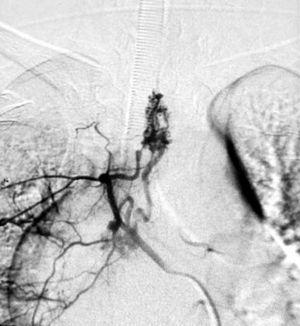

La causa malformativa incluye 2 pacientes (12,5 %) afectados de una malformación arteriovenosa medular de localización C2-C6 en un caso y D6 en el otro. El primero se presentó con cervicalgia que precedió a la tetraplejía mientras que en el segundo el síntoma inicial fue dolor en el hombro que fue seguido por paraparesia. A ambos se les administró metilprednisolona entre las 9 y las 19 h de la lesión y se realizó radiología intervencionista al cuarto día (figs. 1 y 2). Se realizó traqueostomía al paciente con lesión cervical a los 19 días de ingreso. Ambos residen en su casa, uno de ellos con ventilación mecánica domiciliaria.

Figura 2. Arteriografía: malformación arteriovenosa.